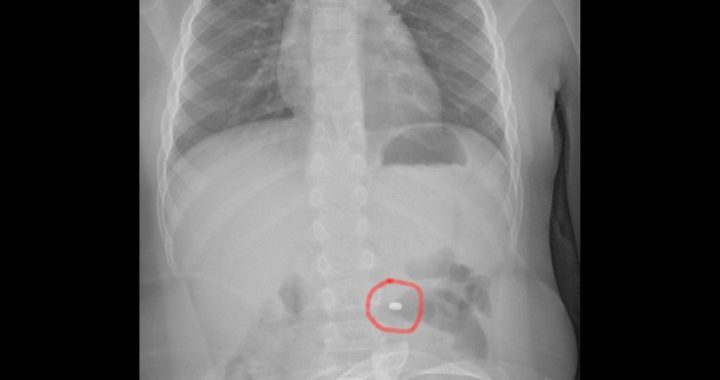

La famiglia, naturalmente spaventata, dopo una prima valutazione al PS della propria città, è stata indirizzata all’Ospedale Cannizzaro di Catania. Qui i medici hanno compreso il pericolo e applicato le linee guida riferite precisamente all’ingestione di una pila a bottone. Eseguita la radiografia dell’addome che ha messo in evidenza la presenza e la localizzazione del corpo estraneo, il bambino è stato condotto in sala operatoria dove gli endoscopisti, con l’assistenza degli anestesisti, hanno potuto estrarre in sicurezza il piccolo oggetto, prima che esso potesse causare conseguenze più importanti. Dopo una notte in osservazione, tornato in piena salute, il bimbo ha fatto rientro a casa con i genitori.